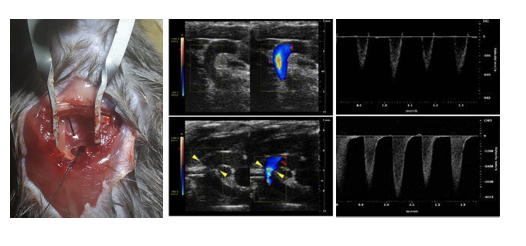

主动脉弓缩窄模型(transverse aortic constriction, TAC)早由Rockman等于1991年正式建立,是慢性心室肥大常用的疾病模型,用于模拟高血压或室内压增高而引起的肥厚性心肌病、心衰。TAC术后,主动脉弓部定量的缩窄引起主动脉血流受阻,左心室压力负荷增加,诱发了左心室的心室肥厚,早期以向心性肥厚为主,心功能可有效代偿,随着时间的延续,进行性发展为心腔的扩张,终发展为心力衰竭。

根据动物品系、基因型和手术缩窄程度的不同,心室肥厚和心衰的进程不同。TAC术后1周可发展为显著性的心室肥厚,2-3周发展为心力衰竭。

案例展示: